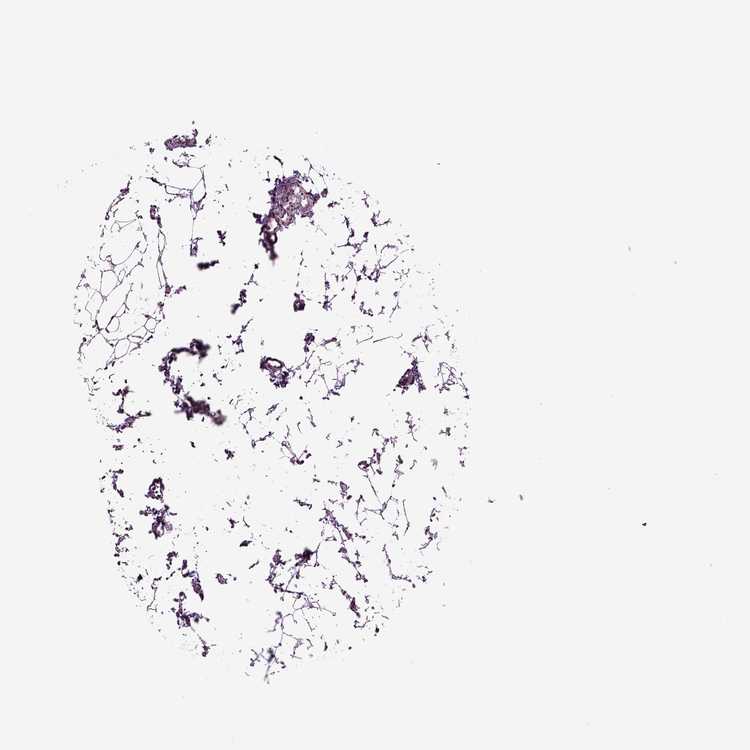

LYMPH NODE - Antibody stainingi

Antibody staining in the annotated cell types in the current human tissue is reported as not detected, low, medium, or high, based on conventional immunohistochemistry profiling in selected tissues. This score is based on the combination of the staining intensity and fraction of stained cells.

Each image is clickable and will lead to virtual microscopy that enables deeper exploration of all samples and also displays staining intensity scores, fraction scores and subcellular localization as well as patient and tissue information for each sample.

Antibody HPA076960

Germinal center cells Medium

Non-germinal center cells Medium